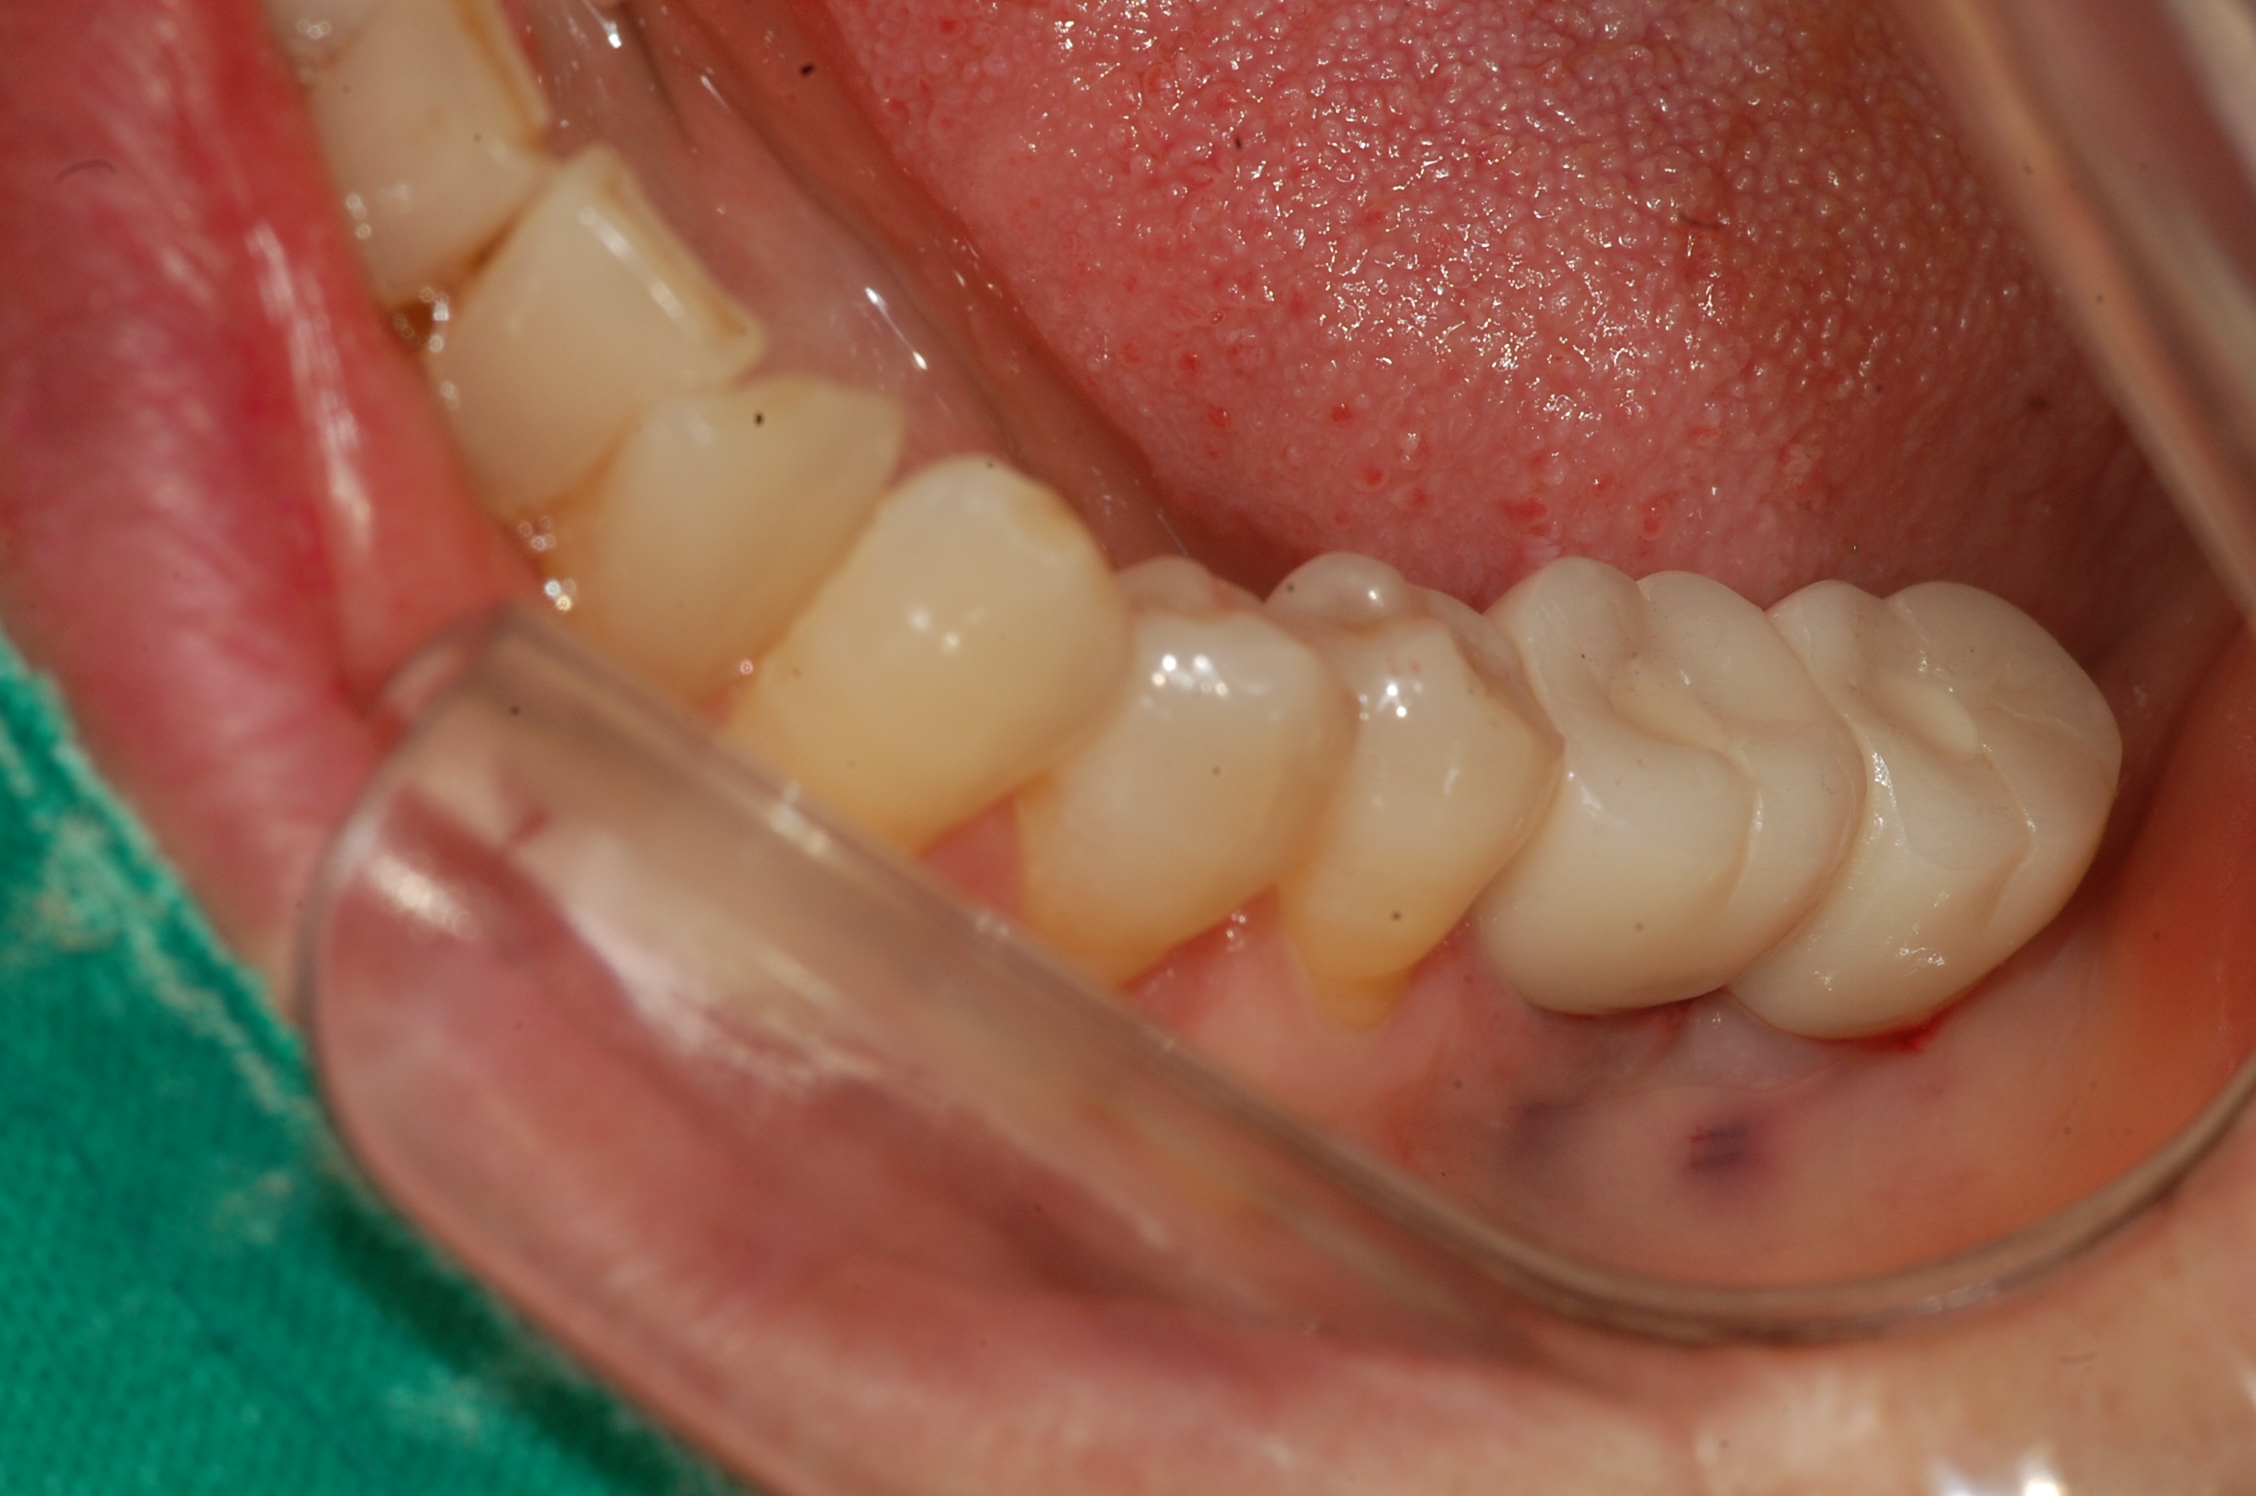

[임플란트] 제목 : 임플란트 지르코니아 보철

구치부 임플란트의 지르코니아 보철 치료 예입니다.